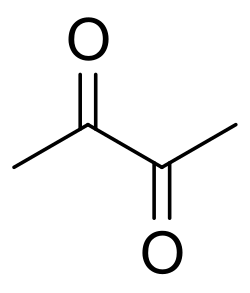

Bronchiolitis obliterans has many possible causes, including collagen vascular disease, transplant rejection in organ transplant patients, viral infection (adenovirus, respiratory syncytial virus, influenza, HIV, cytomegalovirus), Stevens–Johnson syndrome, Pneumocystis pneumonia, drug reaction, aspiration and complications of prematurity (bronchopulmonary dysplasia), and exposure to toxic fumes. Toxins implicated in the condition include diacetyl, sulfur dioxide, nitrogen dioxide, ammonia, chlorine, thionyl chloride, methyl isocyanate, hydrogen fluoride, hydrogen bromide, hydrogen chloride, hydrogen sulfide, phosgene, polyamide-amine dyes, mustard gas and ozone.[4][6][12] It can also be present in patients with IBD, systemic lupus erythematosus, juvenile idiopathic arthritis, rheumatoid arthritis, GERD, IgA nephropathy, and ataxia telangiectasia.[13][14][6] Activated charcoal has been known to cause it when aspirated.[15] The ingestion of large doses of papaverine in the vegetable Sauropus androgynus has caused it.[16] Additionally, the disorder may be idiopathic (without known cause).[17][18][19]

Diacetyl is a chemical used to produce the artificial butter flavoring[25] in many foods such as candy and microwave popcorn and occurring naturally in wines. This first came to public attention when eight former employees of the Gilster-Mary Lee popcorn plant in Jasper, Missouri developed bronchiolitis obliterans. Due to this event, bronchiolitis obliterans began to be referred to in the popular media as "popcorn lung" or "popcorn workers lung".[26][27][28][29] It is also referred to as "flavorings-related lung disease".[30]